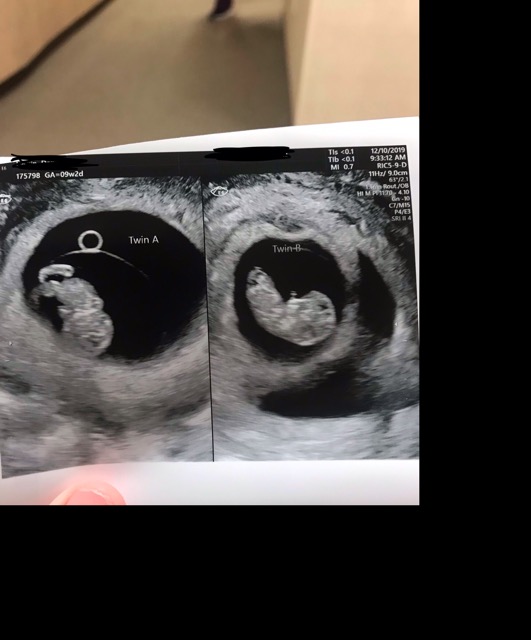

We just got the surprising

news today that we are expecting twins! I was never expecting this because we don’t have twins in our families.